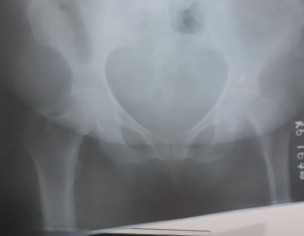

She had a fracture unable to stand and walk we got the first opinion from orthopedic surgeon and adviced for surgery. Looking forward for second opinion and advice .

Yes Pt require surgery.

Needs surgery thanks

when hip bone is fractured, surgery gives best result. she can start walking next day and good recovery.

you can leave it without operation but she will be in pain for long time and will not be able to walk for few weeks.

She does need immediate Surgery. And delay can cause complications and lower success rate.